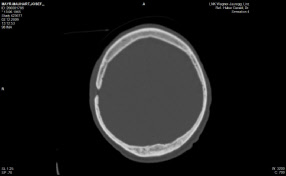

Anbei Daten zur Enthauptung (Heilige Schrift)

Jefferson Fraktur (med. Fachsprache)

Das Bild bekam ich erst vor kurzem

Ist vom 20.11.2017

Bohrlochtrepernation